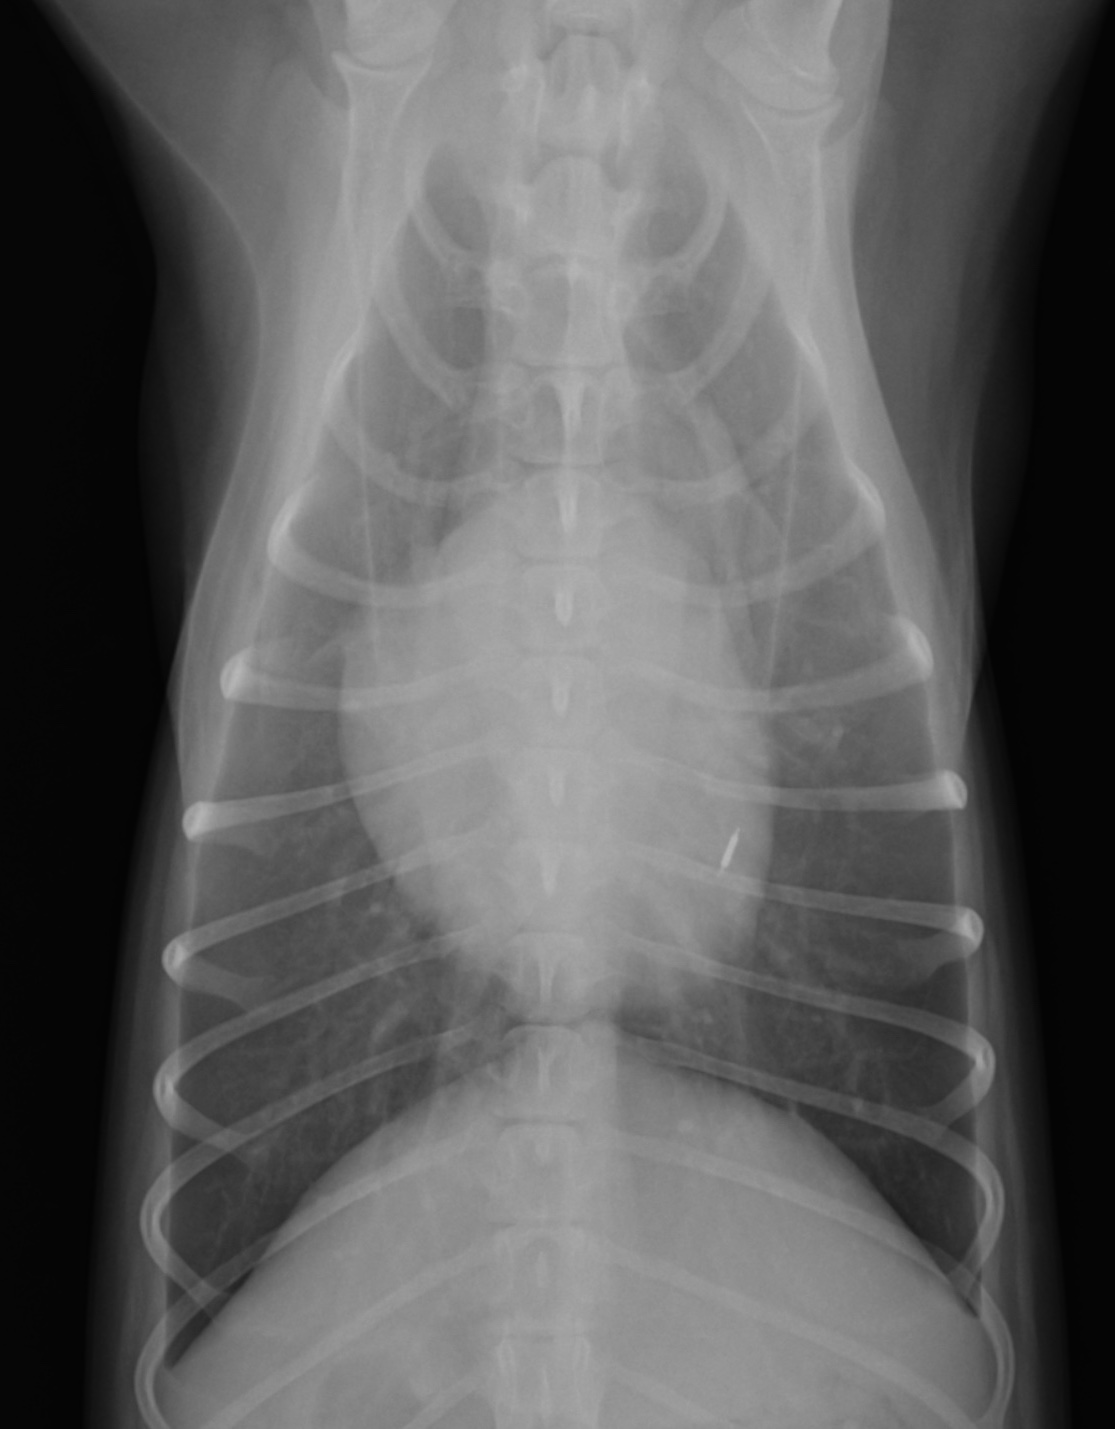

11歳のトイ・プードルちゃん。自宅で急に呼吸が荒くなったため来院されました。聴診にて左側心尖部にLevine Ⅳ/Ⅵの収縮期雑音が認められた。心原性肺水腫が疑われ、画像検査を実施しました。

臨床学的検査を実施し、僧帽弁閉鎖不全症 (ACVIM stage C)による心原性肺水腫と心室中隔欠損症と診断を行い、50%酸素室での入院治療を開始しました。ラシックス(利尿剤)、カルペリチド(血管拡張作用など)の持続静脈内投与、ピモベンダン(強心薬)の静脈注射を中心に行い、肺水腫の改善が認められ退院しました。その後は内服による心臓病のコントロールを行なっています。

心原性肺水腫は命に関わる救急疾患であり、犬の場合多くの原因は僧帽弁閉鎖不全症であります。主な症状は呼吸困難であり、重篤な場合は喀血や咳を伴うこともあります。心原性肺水腫の生存退院率は56~82%と報告されており、内科治療での改善が見込まれない場合は人工呼吸治療を行う場合もあります。